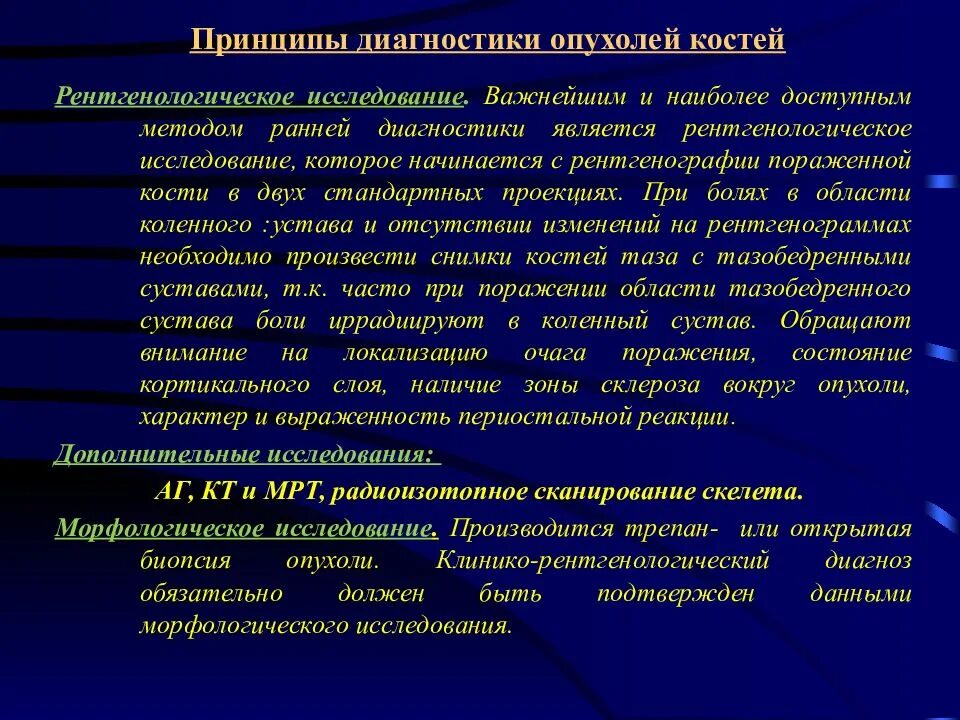

Алгоритм диагностики опухолей. Методы диагностики опухолей костей. Методы выявления опухоли. Методы диагностики злокачественных опухолей. Методы диагностики опухолей. Метод диагностики опухолей. Методы выявления опухоли. Методы диагностики злокачественных опухолей.

Методы диагностики опухолей. Метод диагностики опухолей. Методы выявления опухоли. Методы диагностики злокачественных опухолей.